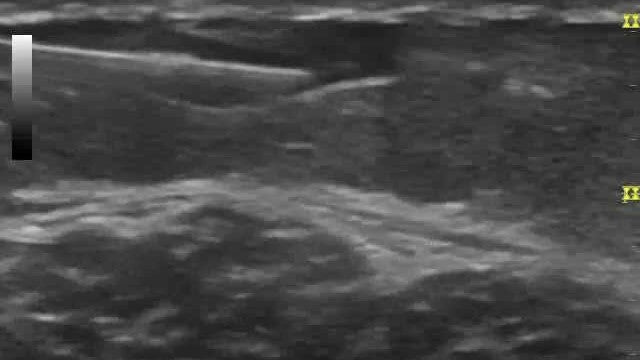

Ultrasound Guided Sclerotherapy

Watch our detailed video on an actual ultrasound guided sclerotherapy session done at Re*be.